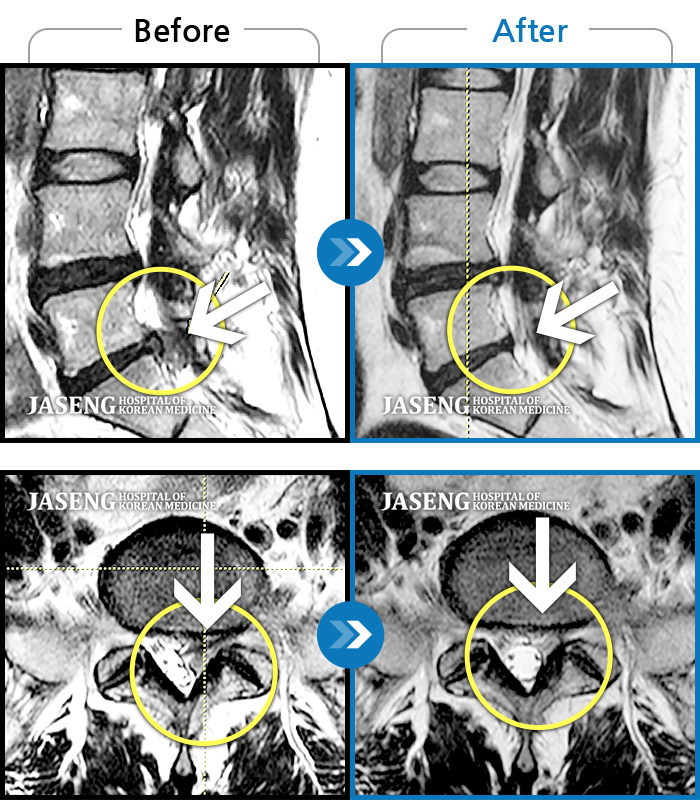

MRI 치료사례

왼쪽 엉덩이의 통증이 심해서 출산 후 일상생활이 힘들어요